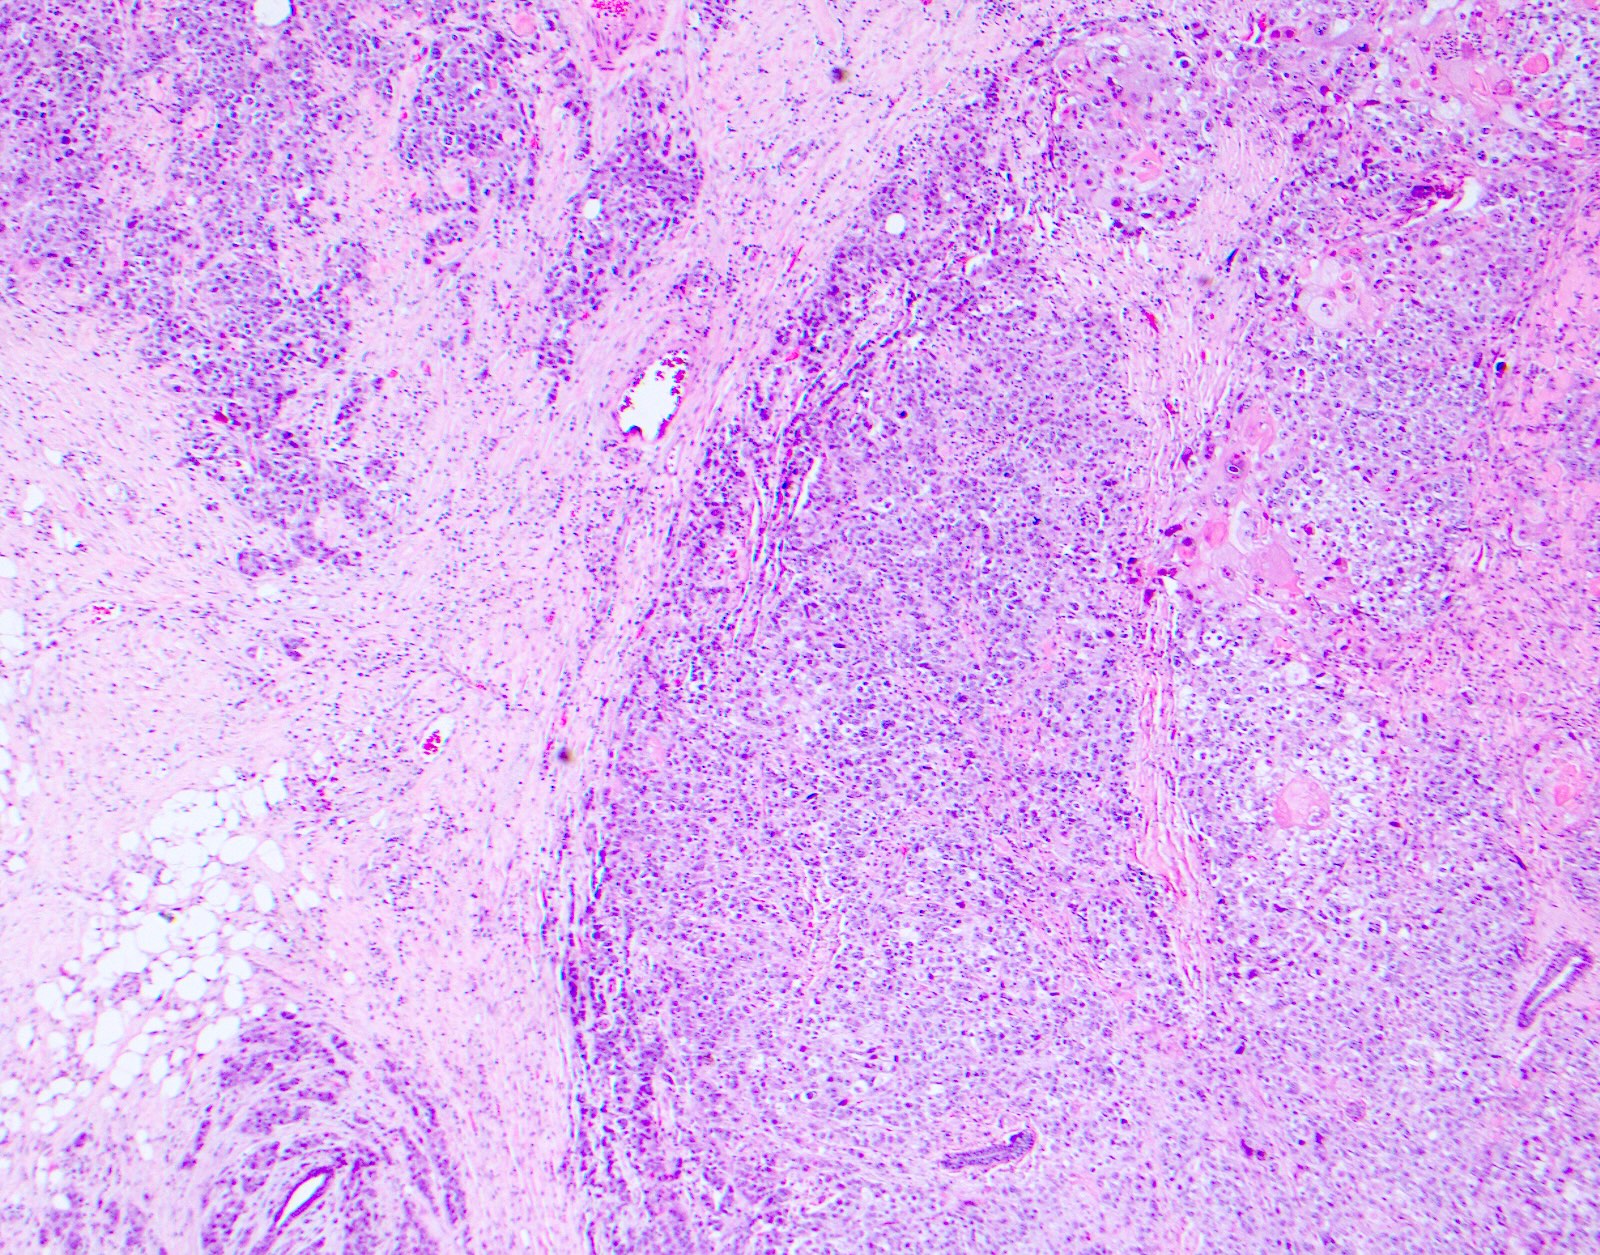

Microscopic (histologic) images

Contributed by Surekha Bantumilli, M.D. and Dimitri G. Trembath, M.D., Ph.D.

- Urinary bladder

- Sensitive positive marker for high grade invasive urothelial carcinoma (Histopathology 2003;42:167)

- Distinguishes dysplasia (basal staining only) from carcinoma in situ (stains all urothelial layers) (Hum Pathol 2000;31:745)

- Diffuse staining in both intraductal and invasive urothelial cancer (Am J Surg Pathol 2022;46:454)